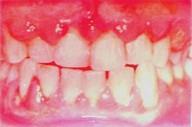

问题 急性牙龈脓肿无哪项症状 ( )

选项 A.体温升高,局部淋巴结肿大 B.患牙及邻牙均对叩诊敏感 C.口腔粘膜往往普遍红肿,出现溃疡和假膜 D.外周血白细胞计数升高 E.多数牙间乳头的红肿和跳动

答案 C